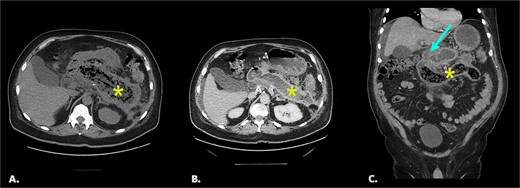

On initial CT imaging, avascular phlegmon and necrotic pancreatic tissue were observed in the expected retroperitoneal location of the pancreas (Fig. 1A).

(A) Initial non-contrast CT. Axial image shows extensive pancreatic necrosis and phlegmon (*). 1B/C Follow up CT with IV contrast (portal venous phase). Image 1B: axial image shows fluid replacement of tissue in the pancreatic bed (*). Image IC: coronal image shows fistula between pancreatic bed and duodenum (arrow) and bezoar in the distal duodenum (*).

On follow-up CT imaging, the pancreatic bed was fluid filled with tubular, avascular mottled material in the distal duodenum, representing pancreatic bezoar (Fig. 1B and1C).